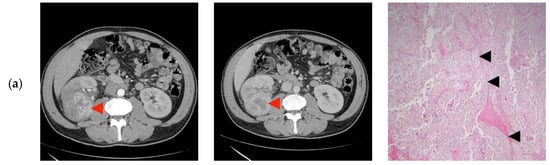

None of the patients had tumor invasion of the renal vein or the adjacent organs, calcifications, or macroscopic fat (Figure 2).

Figure 2.

Computer tomography findings in the cortico-medullary and nephrographic phases; Histopathological examination (a) Heterogeneous peripheral contrast enhancement, like the renal cortex (◄); Clear Cell RCC, Fuhrman grade 2. Tumor with compact and alveolar architecture (◄) of cells with clear cytoplasm, distinct cell boundaries and nuclei with nucleoli prominent at 100×. (b) Moderate nodular enhancement (◄); Clear Cell RCC, Fuhrman grade 1. Tumor with alveolar (←) and tubular architecture (◄) of cells with clear cytoplasm, distinct cell boundaries and nuclei with inconspicuous nucleoli at 100×. (c) Faint intra-tumoral contrast enhancement with mild progression in the nephrographic phase (◄); Papillary-RCC, type II. Tumor with papillary architecture (*) with pseudostratified layers (◄) of large cells with abundant eosinophilic cytoplasm, atypical nuclei with prominent nucleoli at 100×. (d) Heterogeneous contrast enhancement, less than the renal cortex in both phases, with an important necrotic component (◄); Adult cystic nephroma. A tumor composed of various sized cysts (◄) lined by flat cells separated by fibrous septa that contain smooth muscle (*) at 100×. (e) Intense contrast in the cortico-medullary phase, with an apparent central “scar” (◄) and less contrast enhancement compared to the renal cortex in the nephrographic phase; Clear Cell RCC, Fuhrman grade 1. Tumor with alveolar (*) and tubular (◄) architecture of cells with clear cytoplasm, distinct cell boundaries, and nuclei with inconspicuous nucleoli at 100×. (f) Bulky exophytic tumor with nodular peripheral contrast enhancement, like the renal cortex on the cortico-medullary phase and less than this on the nephrographic phase (◄); Clear Cell RCC, Fuhrman grade 2. Tumor with alveolar (*), tubular (◄) and cystic (o) architecture of cells with clear cytoplasm, distinct cell boundaries, and nuclei with nucleoli prominent at 100×. (g) Peripheral contrast enhancement like the renal cortex with an apparent “central scar” (◄) on the cortico-medullary phase and wash-out on the nephrographic phase, with the persistence of the “central scar”; Multicentric Chromophobe-RCC. Flocculent cytoplasm that condenses around the edges (“plant cell-like”, ◄) and pleomorphic nuclei (←) at 400×. (h) Faint peripheral enhancement on both phases (◄); Clear Cell RCC, Fuhrman grade 1. Tumor with the alveolar architecture of cells with clear cytoplasm (*), distinct cell boundaries (←), and nuclei with inconspicuous nucleoli at 100×. (i) Bulky tumor with peripheral enhancement (◄), like the renal cortex in the cortico-medullary phase, with progressive filling in the nephrographic phase; Clear Cell RCC, Fuhrman grade 2. Tumor with alveolar architecture (*) of cells with clear cytoplasm, distinct cell boundaries and nuclei with nucleoli prominent at 100×. (j) Faint spotted intra-tumoral enhancement on both phases (◄); Multiloculated cystic RCC, Fuhrman grade 1. Tumor with cystic architecture (*), with thin fibrous septae (◄) lined by clear cells (←). Tumor cells with inconspicuous nucleoli at 100×. (k) Faint, spotted intra-tumoral enhancement on both phases (◄); Metanephric adenofibroma. A tumor composed mainly of tightly packed tubules (◄) and secondarily long branching and angulated ducts (←). Tumor cells have scant cytoplasm and nuclei are small with no nucleoli, with no mitotic figures. Stroma is present as significant fibrous septa (*) at 100×. (l) Peripheral enhancement is like the renal cortex with the presence of a central non-enhancing area (“central scar”) (◄), on both phases; Oncocytoma. Small oncocytic cells (◄) with round, regular nuclei, no mitosis at 200×. (m) Peripheral enhancement like the renal cortex on the cortico-medullary phase and discretely less than the renal cortex on the nephrographic phase (◄); Clear Cell RCC, Fuhrman grade 1. Tumor with alveolar architecture (*) of cells with clear cytoplasm, distinct cell boundaries, and nuclei with inconspicuous nucleoli. The tumor invades a segmental renal vein (◄) at 100×. (n) Discrete nodular, peripheral enhancement (◄), less than the renal cortex on both phases; Papillary RCC, type I. Tumor composed of small cuboidal cells, with scant cytoplasm and round nuclei without nucleoli, arranged on a single layer on papillary cores (◄). Some of the papillary cores contain foamy macrophages (←) at 100×. (o) Peripheral enhancement less than the renal cortex on both phases (◄); Clear Cell RCC, Fuhrman grade 1. Tumor with a compact and alveolar architecture of cells with clear cytoplasm (←), distinct cell boundaries, and nuclei with inconspicuous nucleoli at 100×. (p) Bulky tumor with peripheral enhancement, less than the renal cortex on both phases (◄), with wash-out in the nephrographic phase; Clear Cell RCC, Fuhrman grade 1. Tumor with alveolar architecture (*) of cells with clear cytoplasm, distinct cell boundaries, and nuclei with inconspicuous nucleoli at 100×.